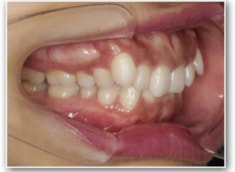

叢生+左下1番先天欠如ケース

治療法:裏側の矯正(リンガルブラケット:舌側矯正)

治療前